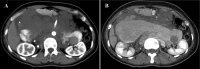

Intra-abdominal venous malformations and inferior vena cava aneurysms are rare and difficult to diagnose because of their nonspecific clinical symptoms. These vascular anomalies are important entities due to the risk of thrombosis or rupture. According to the classification of International Society for the Study of Vascular Anomalies, venous malformations are classified as low-flow vascular anomalies, showing absence of arterial and early venous enhancement and slow gradual filling with contrast on delayed venous imaging. Phleboliths related to thrombosis and calcifications, are the key finding of venous malformations. In this article, we report an exceptional case of large intra-abdominal venous malformations in associated with an inferior vena cava aneurysm.